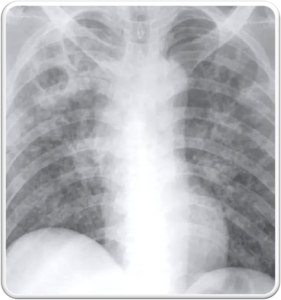

• Miliary TB refers to widespread dissemination of TB by hematogenous spread.

• Seen more frequently in reactivation TB.

The characteristic radiographic and high-resolution CT findings consist of innumerable, 1- to 3-mm diameter nodules randomly distributed throughout both lungs